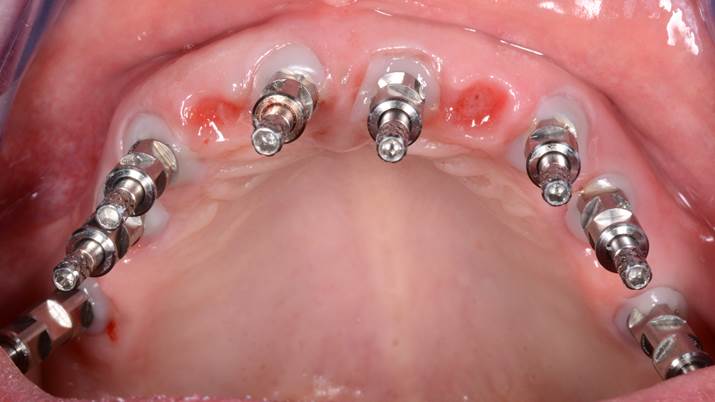

Clinical case: Extraction of all teeth in upper maxilla,

immediate implant placement, & provisionalization

- Courtesy of Dr. Iulian Filipov, Romania -

Keywords

AnyRidge, immediate placement, immediate provisionalization, maxillary fully edentulous case, initial stability, edentulous, Dr. Iulian Filipov, R2GATE, MEGA ISQ

Products:

AnyRidge implant system, Mega ISQ, R2GATE

“AnyRidge ensures long-term biological stability

& functionality even in

full-mouth rehabilitation case. ”